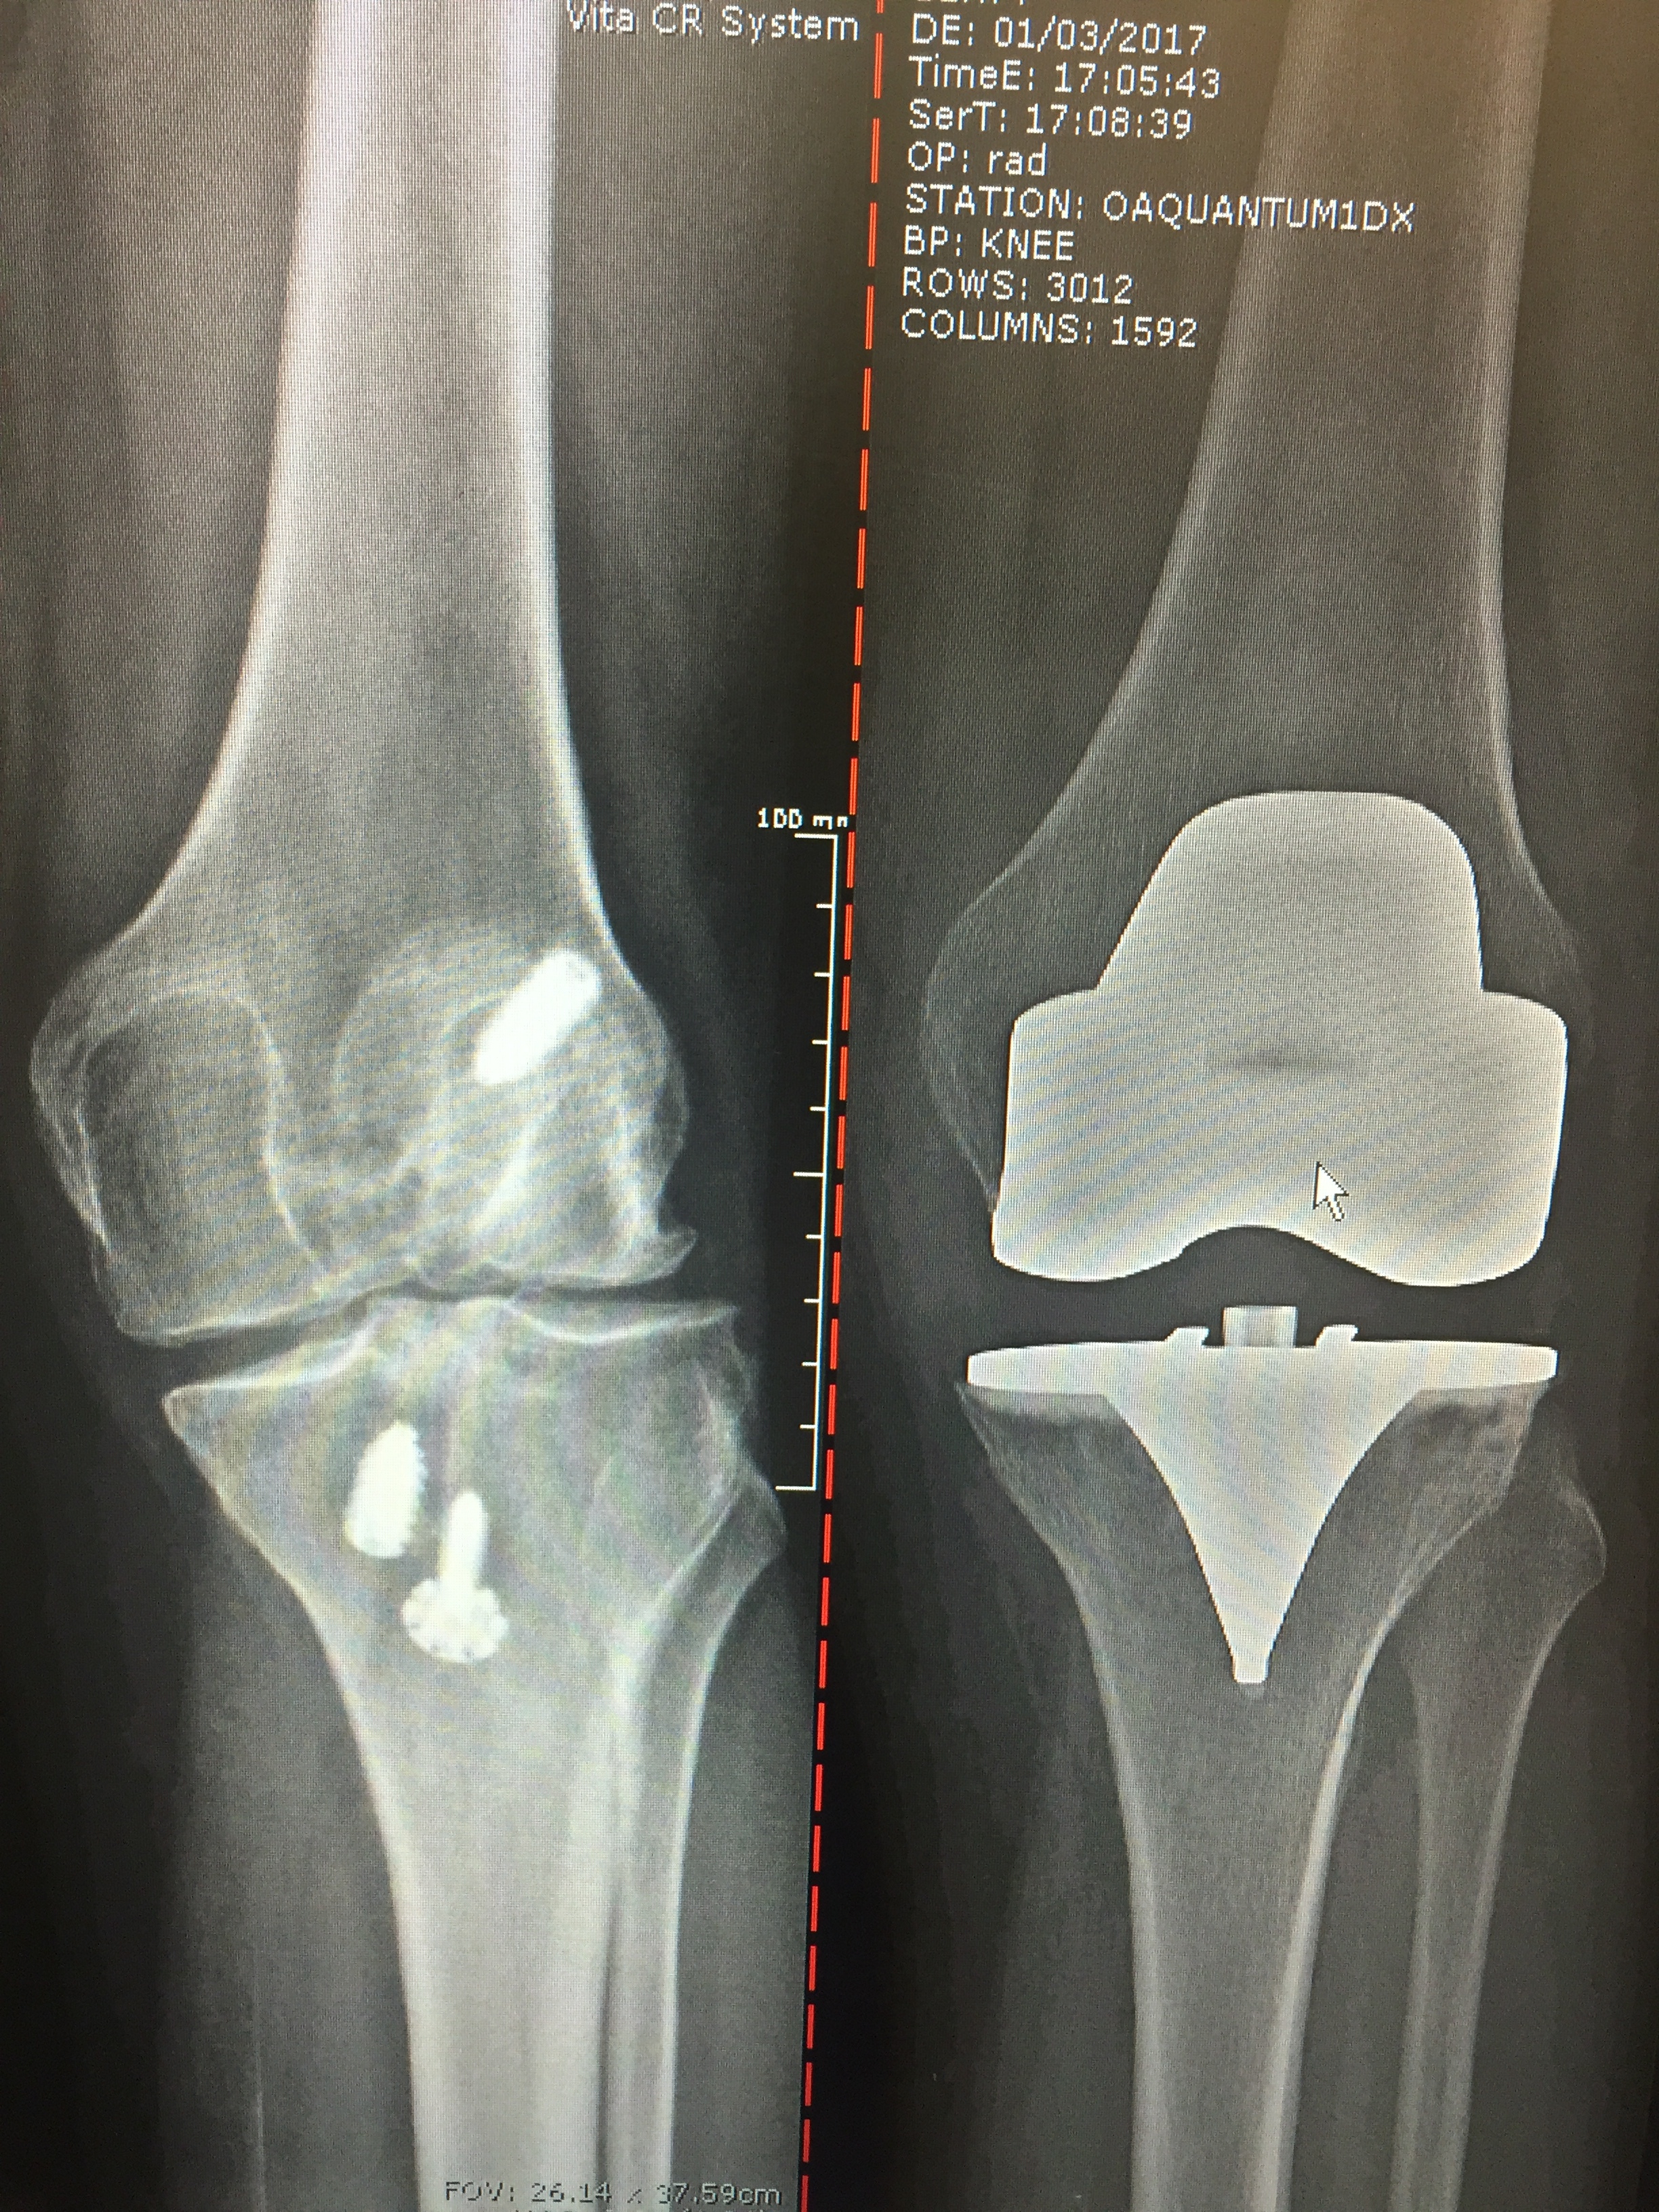

Before: Post traumatic knee arthritis with retained screws, rod, wires and deformity

After: Complex Total Knee Replacement - leg now straight

BIOMET REVISION